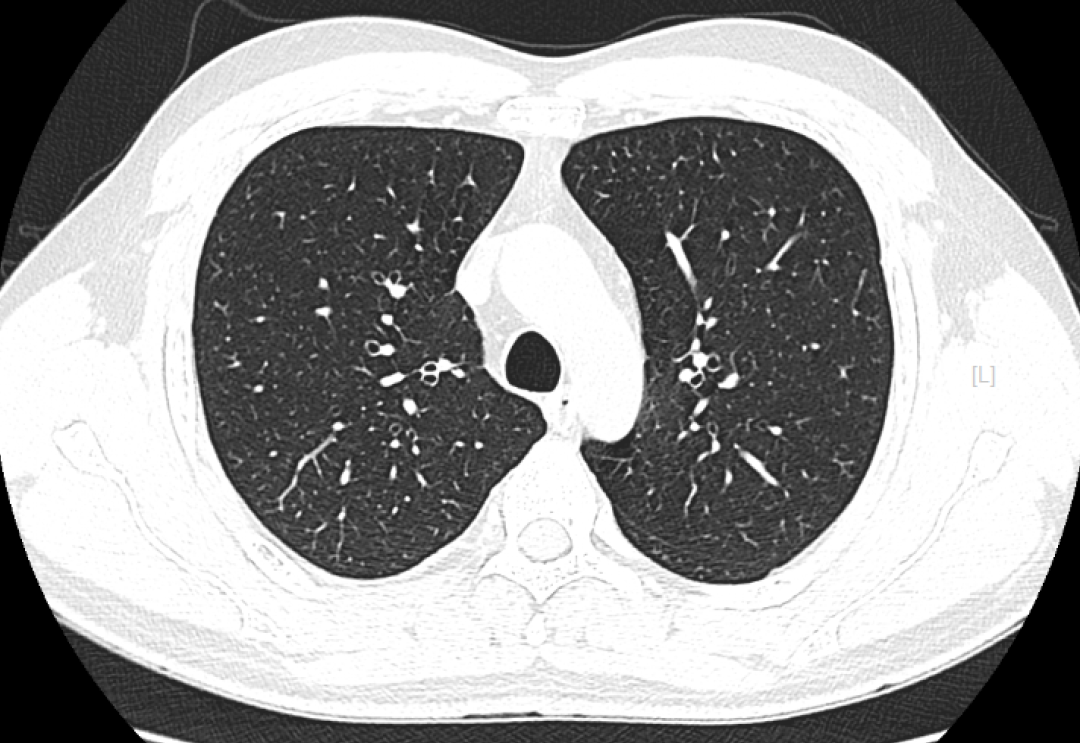

CT检查成像原理与DR类似,使用的是X射线,之后通过计算机成像。相较DR,CT可以多角度、多层面、多功能扫描成像,就像把一个面包切成多个平面进行观察。

检查应用范围:从头到脚,均可进行CT平扫,主要运用于头颅、颈部、胸部、腹部、脊柱、盆腔、四肢等部位。特别是高分辨率胸部CT,在检查肺部小结节时,运用非常广泛,CT检查脑出血也有相当的优势,另外微小的骨折、大部分器官的病变都能够看到。

优点:相较DR,CT的密度分辨率更高,可以显示DR检查不能发现或容易遗漏的病变。

而CT检查是把面包切片来看,获得的是真正的断面图像,没有层面以外的结构干扰。虽然细节看的更清楚了,但它就不是一块完整的面包了。